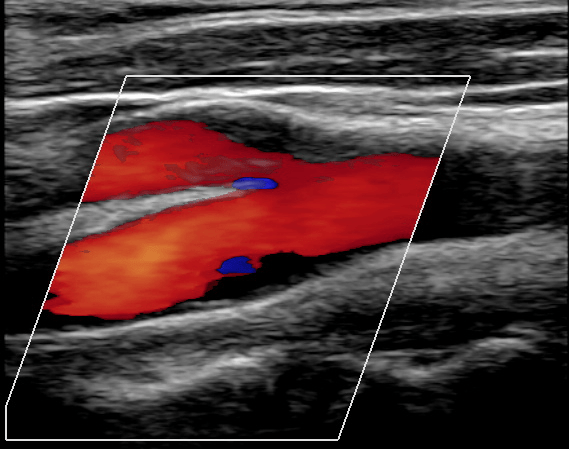

Ecografia Vascular de Artérias Carótidas e Vertebrais

A Ecografia Vascular de Artérias Carótidas e Vertebrais é um exame que avalia através do ultrassom a anatomia e circulação sanguínea dessas artérias, que levam o sangue em direção ao cérebro. Este exame permite investigar a presença de doença aterosclerótica (“placas de gordura”), aneurismas, dissecções e outras doenças que podem acometer as artérias carótidas e vertebrais.

O paciente permanece deitado sobre a maca enquanto o médico realiza a avaliação com o ultrassom sobre a região cervical do paciente.